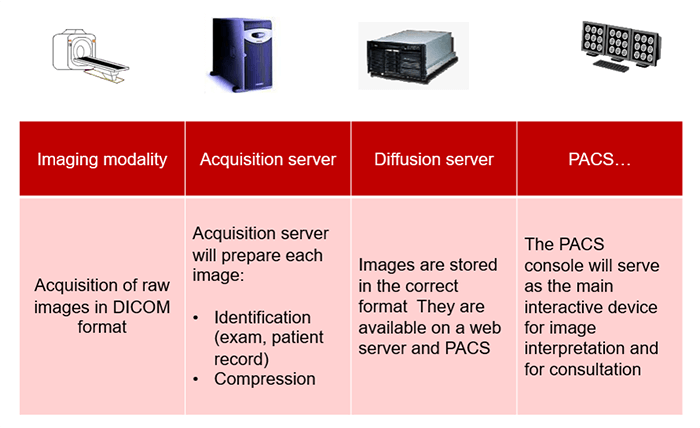

This simplified diagram indicates the image data flow between the imaging modality and PACS.

PACS is usually an integration of input from digital devices which may be any radiological modality. These devices include Image acquisition device, image storage server for short or long term storage of data, transmission network, display station, imaging work station, and user interface, camera to convert to hard copies images on a need basis, and integration to radiology information system and hospital information system.

Acquisition

This simplified diagram indicates the image data flow between the imaging modality and PACS.

- Flow: Modalities -> PACS

The flow of “raw” format images. Acquisition protocol for each modality (automation and technologist dependent).